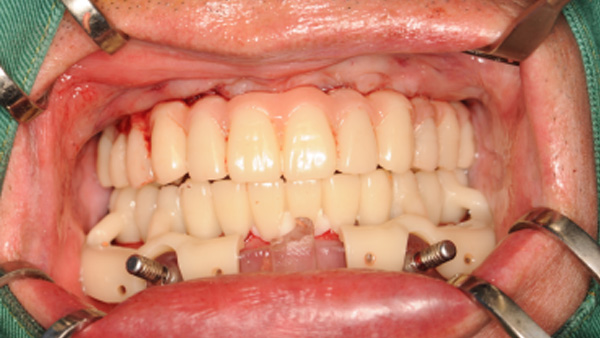

覆蓋所有牙位、即刻種植、即拔即種、全口無牙頜種植